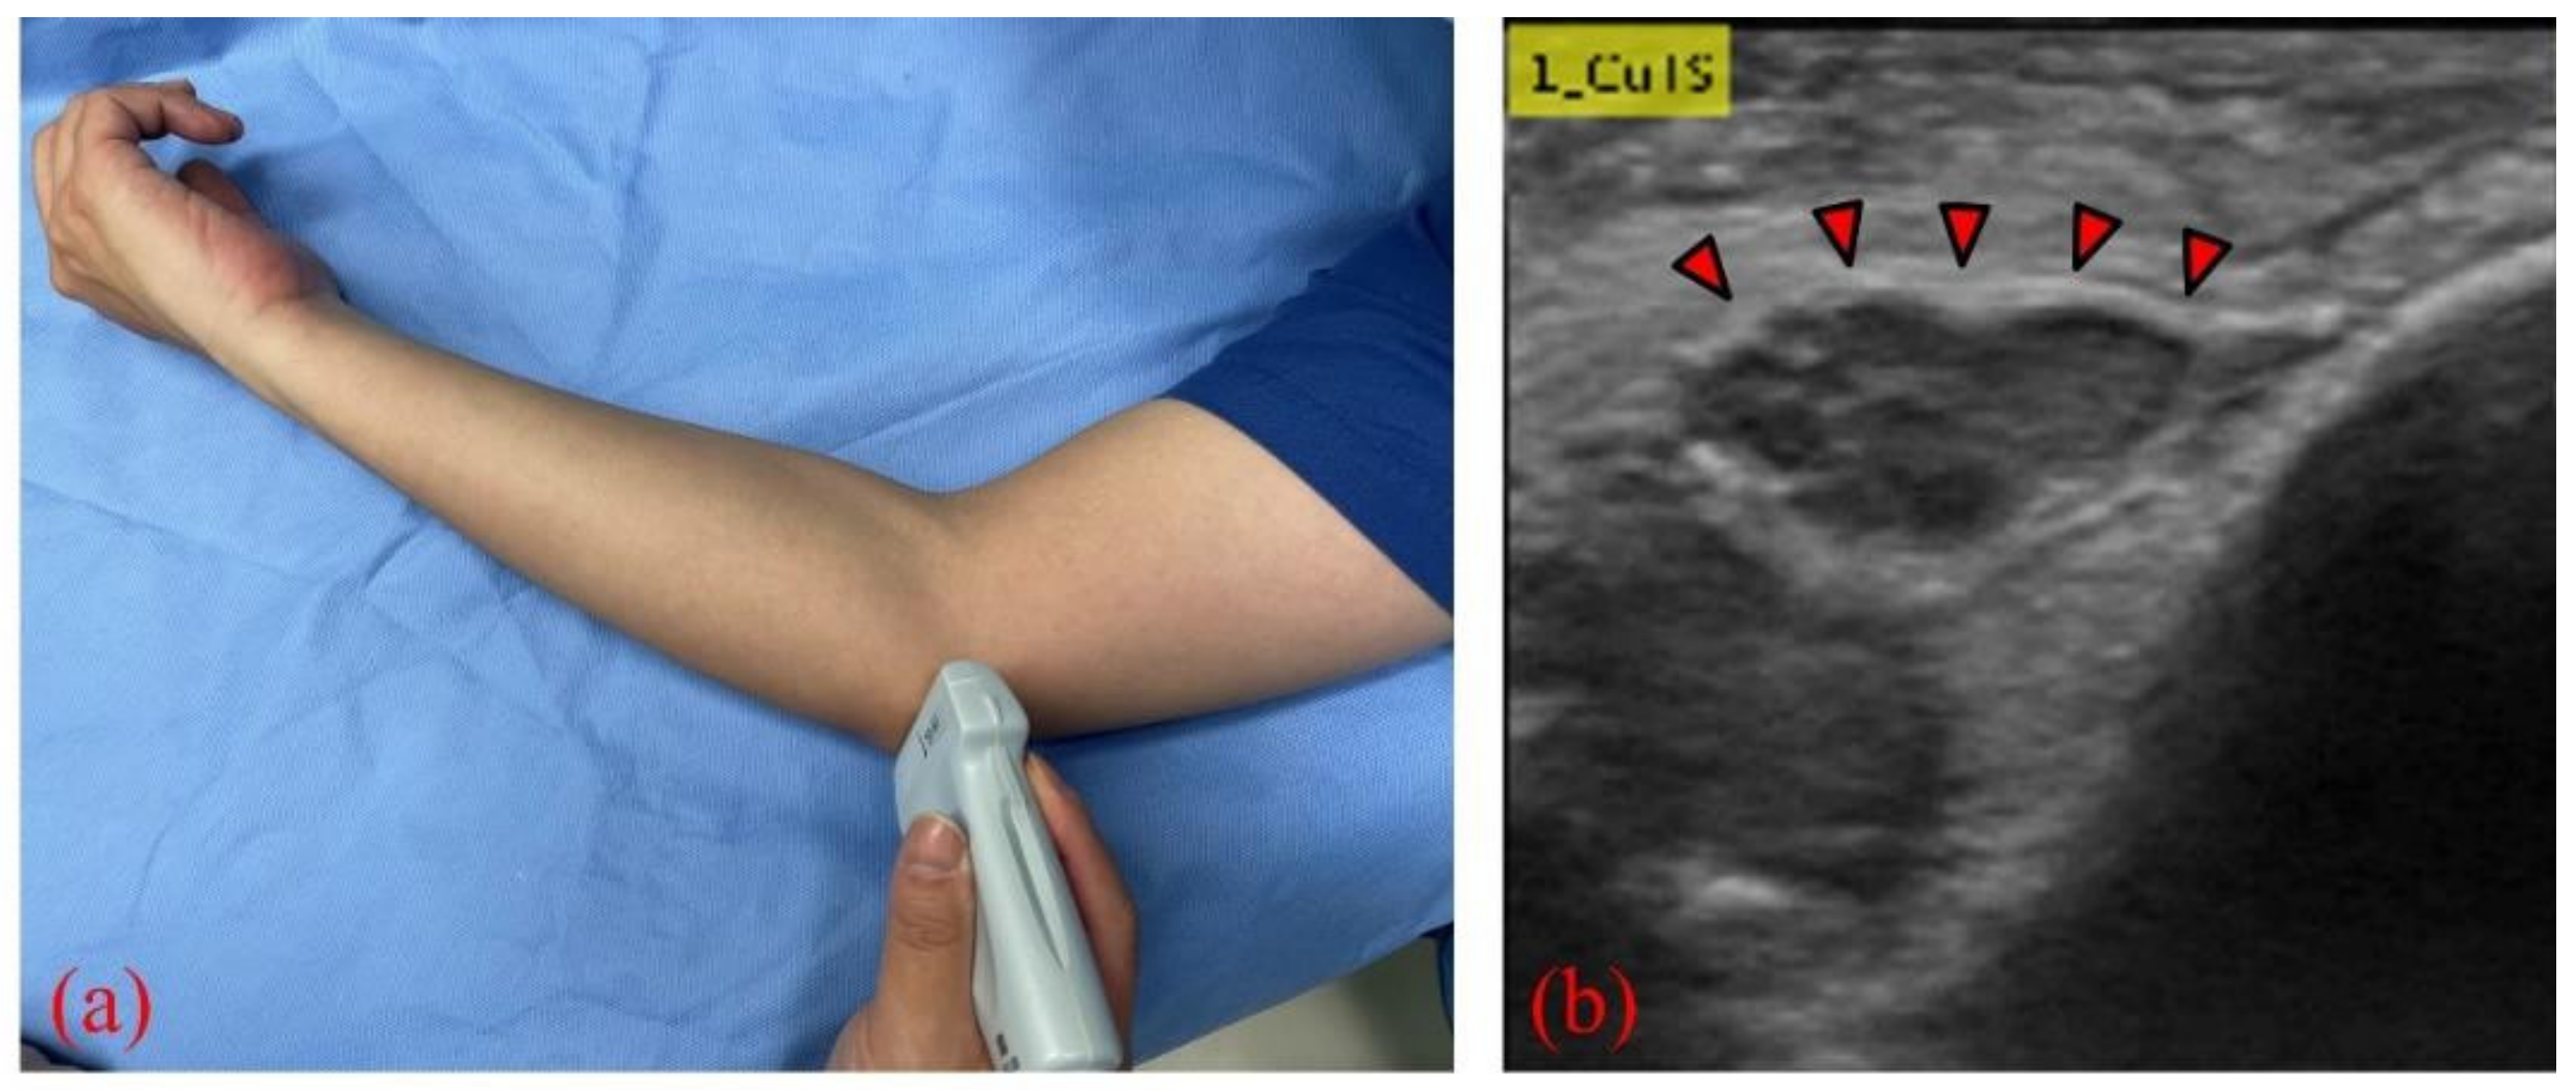

From www.mdpi.com

Diagnostics Free FullText Diagnosis of Cubital Tunnel Syndrome Do X Rays Show Cubital Tunnel Syndrome Mri plays an important role in cases with clinically suspected cubital tunnel syndrome as it confirms the diagnosis and can detect the. Electrodiagnostic testing, magnetic resonance imaging, and ultrasound evaluation have all been shown to be effective in. The ulnar goes from your neck down your arm and to your. Transverse us shows a severely enlarged (22 mm²) ulnar nerve. Do X Rays Show Cubital Tunnel Syndrome.